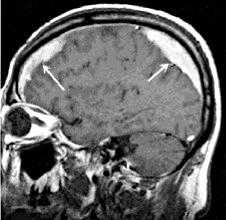

МРТ позволяет четко визуализировать смещенную твердую мозговую оболочку, в виде гипоинтесивной линии на Т1 и Т2 последовательностях, что помогает отдифференцировть эпидуральную гематому от субдуральной.

Остая эпидуральная гематома имеет изоинтенсивный МР сигнал на Т1 ВИ и может иметь различную интенсивность МР сигнала на Т2 последовательностях.

Ранняя подострая эпидуральная гематома гипоинтенсивна на Т2 изображениях, в то время как поздняя и хроническая эпидуральная гематома будут иметь гиперинтесивный МР сигнал как на Т1 так и на Т2 последовательностях.